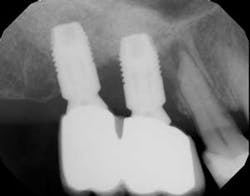

This is a scenario that has happened in practice and, yet, looking back at the radiographs and clinical pictures, there was one big oversight. The adjacent tooth next to the implant had pathology. As clinicians, it can be easy to focus on the area of treatment. When examining post-implant placement radiographs, bone levels are often the first thing we examine. After restoration, we look at excess cement, abutment fit, crown fit, and bone levels. All of these factors are important, but just as important is to examine the status of the adjacent tooth (or implant) and check for periapical radiolucencies and/or dental caries.

There have been numerous case reports in the literature demonstrating infections of dental implants caused by pathology from the adjacent natural tooth. (1) These infections from adjacent teeth can travel quite quickly to the proximal dental implant (figures 1a and 1b) and cause a rapid degree of bone loss. Treatment can consist of loss of teeth, loss of the dental implants, and/or costly regenerative repair (figure 2). (2) This situation is highly preventable if detected early and endodontic therapy is initiated.

The next time you take a post-placement radiograph, look at the adjacent tooth—especially the apex.